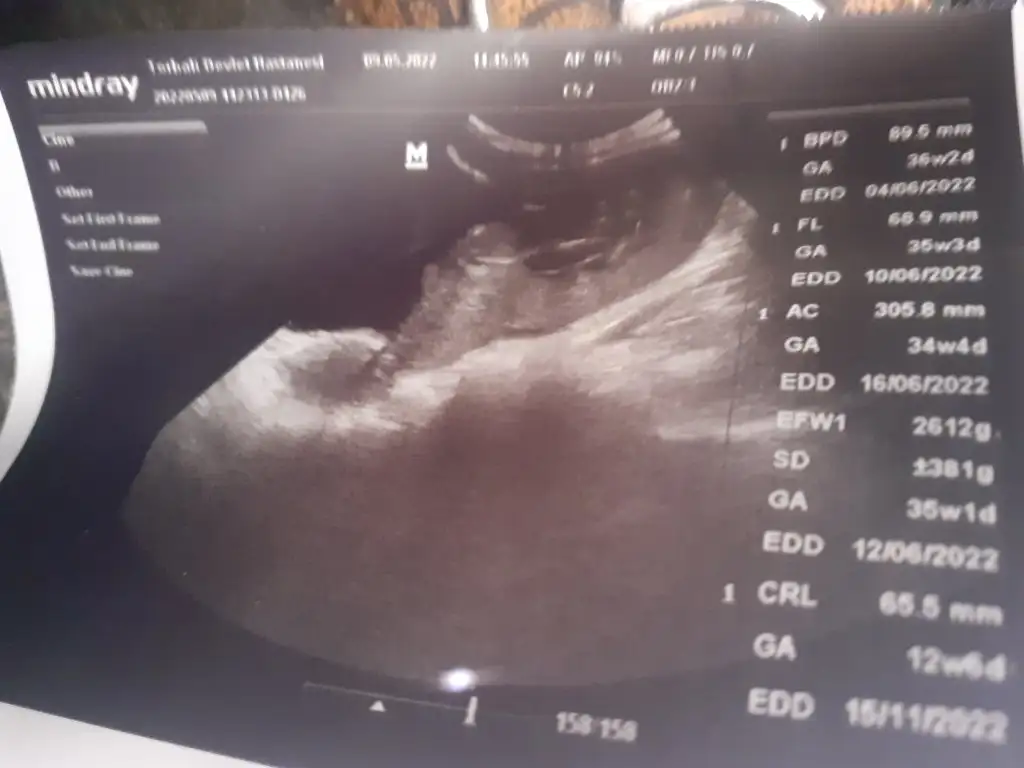

Bakarmisin

• 20220509_153718.webp

20220509_153718.webp

21,1 KB · Görüntüleme: 44

• 20220509_153714.webp

20220509_153714.webp

21,5 KB · Görüntüleme: 39

• 20220509_153706.webp

20220509_153706.webp

23,3 KB · Görüntüleme: 38

• 20220509_153651.webp

20220509_153651.webp

22,5 KB · Görüntüleme: 43